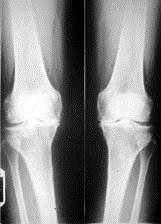

问题 病历摘要: 患者女性,65岁,双膝关节疼痛畸形,伸直受限10分钟,加重3个月。查体:双膝关节呈内翻畸形,双膝关节屈曲90受限,伸直受限,实验室检查正常,癤线见图: 根据病史和检查,该患者最佳的治疗方案是:

选项 A、双膝关节滑膜切除术 B、双膝关节游离体摘除术 C、双胫骨截骨矫形术 D、双膝关节关节镜冲洗打磨术 E、双膝关节全膝关节置换术

答案 E